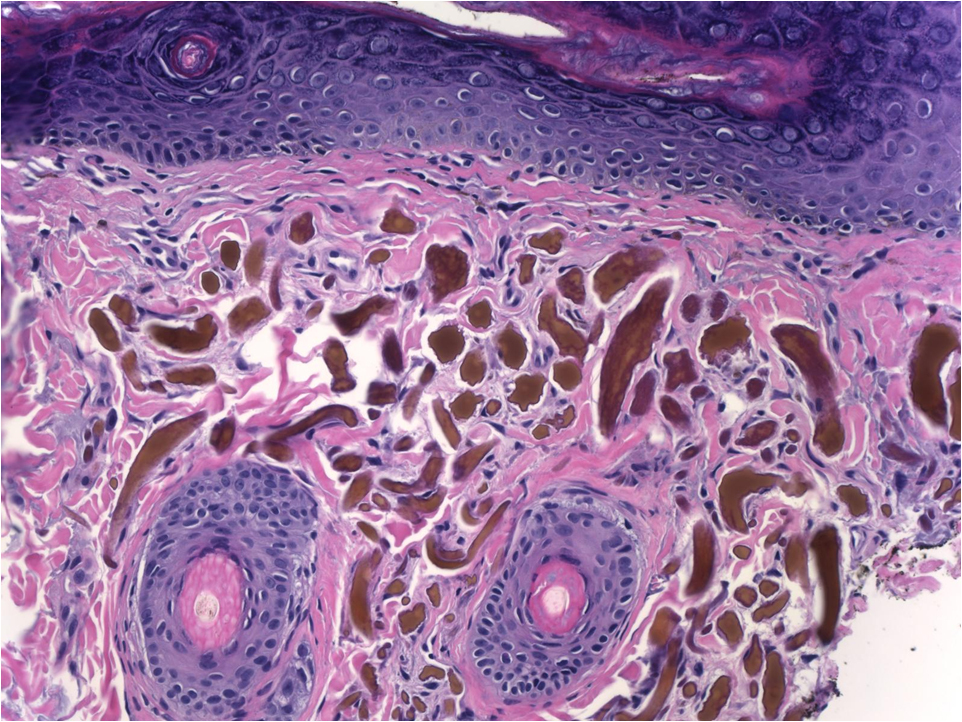

This presented as a papule with a tuft of hair on the face, what is this neoplasm?

Trichofolliculoma

Trichofolliculoma: Most often occurs on the face as a papule with a tuft of hair. Histologically composed of a central dilated large follicle (Mama hair), from which many secondary smaller hair follicles radiate (Baby hairs), with the entire unit often enveloped in a vascularized fibrotic stroma. If sebaceous glands are associated with the hair follicles then the term used is a sebaceous trichofolliculoma or a Folliculosebaceous cystic hamartoma. Within the mesenchymal stroma there are increased CD34 and factor XIIIA fibroblasts and Merkel cells as is seen in the ORS of the follicles.